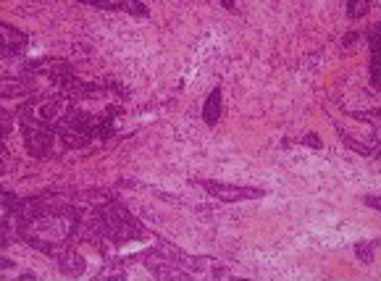

Tumor-associated stroma contribute to cancer growth and progression by promoting stromal–epithelial paracrine signaling. However, only few stromal signatures were developed and found to be prognostic especially in the HER2 breast cancer subgroup.

This project aims to explore the effect of stromal reactivation on the efficacy of different anti-HER2 treatments (alone and combined) in a tractable co-culture and xenografts models